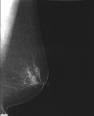

簡介乳房攝影

2007/3/15